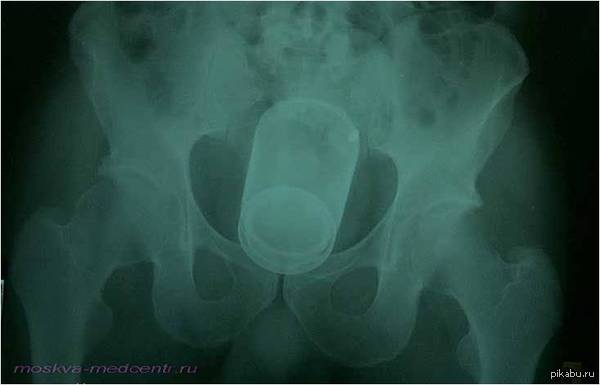

MDPhD Здоровье Это Вам, доктор! (фото здесь изначально было другим - момент извлечения данного инородного тела. Поменял из-за шока пикабушников)) 11 лет назад С праздником, дорогие коллеги! Работы вам без таких подарков! Простите за цинизм. Праздник Медики Извращенцы